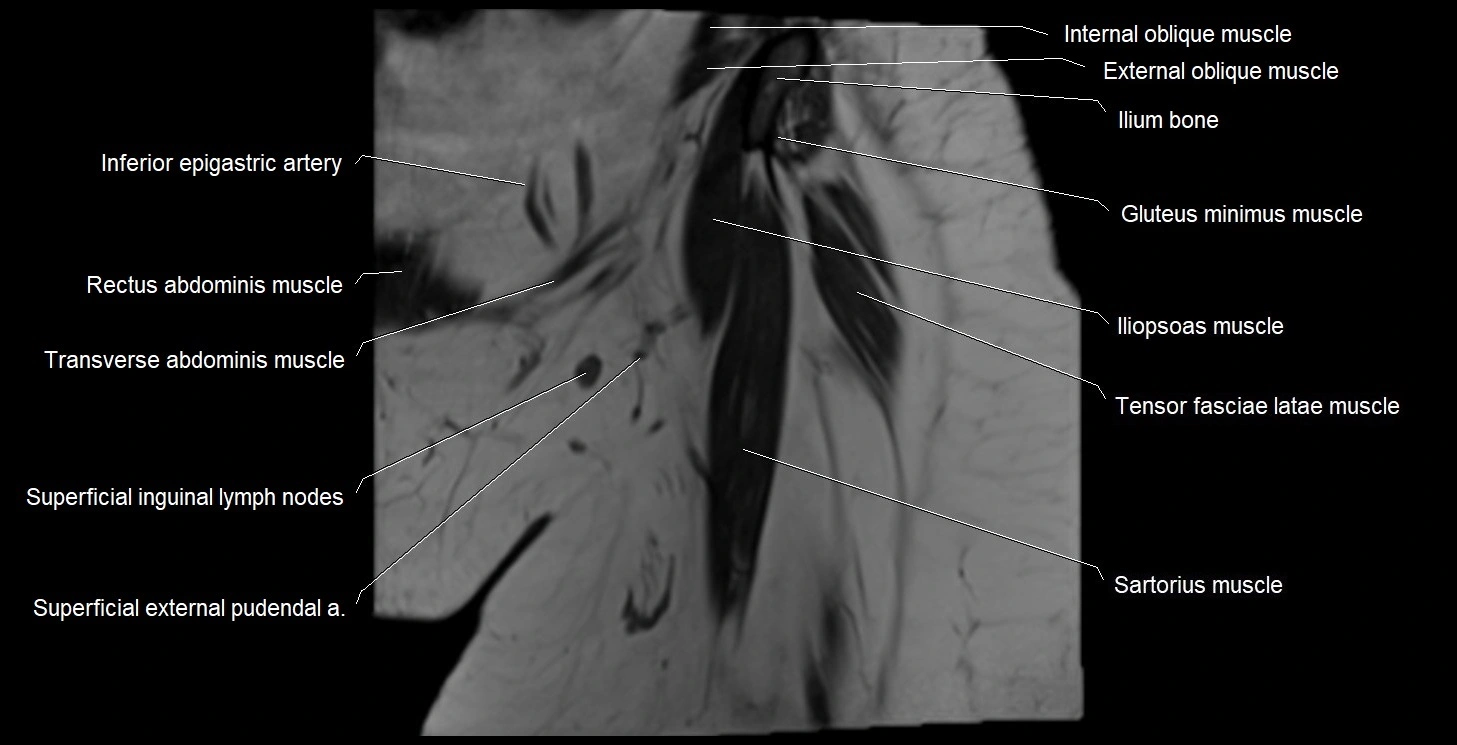

- Inferior epigastric artery

- Iliopsoas muscle

- Gluteus minimus muscle

- Tensor fasciae latae muscle

- Sartorius muscle

- Superficial inguinal lymph nodes